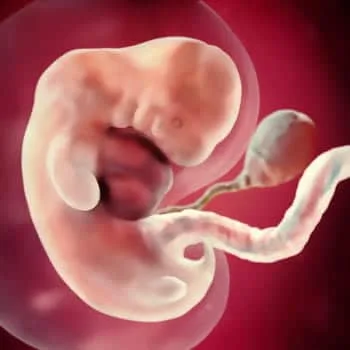

مادر عزیزم حالا من (جنین) بیشتر شبیه به یک بچه شدهام.

اندازه جنین در هفته هفتم

با یک قد ۹ میلیمتری که بهاندازه یک دانه برنج است.

سر من به روی سینه، و بهطرف جلو خم میشود و دستها و پاهایم در این ماه ظاهر میشوند.

بیدلیل نیست که این ماهبهماه چهره معروف است، زیرا چهرهی من بهتدریج مشخص میشود; و در سر من حفرههایی برای دو چشم، دو گوش، بینی و دهان در حال تشکیل شدن است.